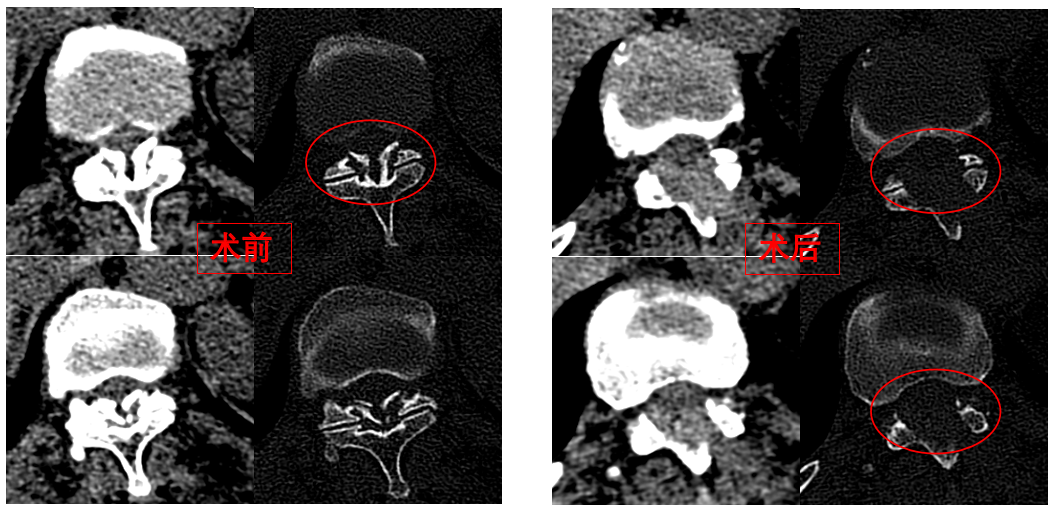

華西醫(yī)院成辦分院骨科副主任醫(yī)師張斌接診后,憑借豐富的脊柱治療經(jīng)驗,立即安排卓瑪阿媽做了系列精密檢查,檢查結(jié)果顯示,阿媽胸椎11/12節(jié)段黃韌帶嚴重骨化,導致椎管顯著狹窄,脊髓受壓,確診為嚴重的“胸椎黃韌帶骨化癥”,如果不及時手術(shù)最終可能面臨癱瘓的風險。

手術(shù)歷時一個半小時,骨科脊柱微創(chuàng)團隊成功完整切除了壓迫脊髓的骨化黃韌帶,徹底解除了卓瑪阿媽的脊髓壓迫。手術(shù)過程順利,手術(shù)切口僅1厘米。

圖為卓瑪阿媽術(shù)前、術(shù)后胸椎CT照片對比。